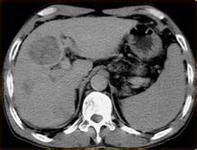

间充质性软骨肉瘤是一种罕见的恶性软骨性肿瘤,多发生于青壮年。Lichtenstein等于1959年首例报道,而Dowling于1964年报道了首例起源于软组织的间充质性软骨肉瘤。直至1996年国外文献报道不足200例。[1]